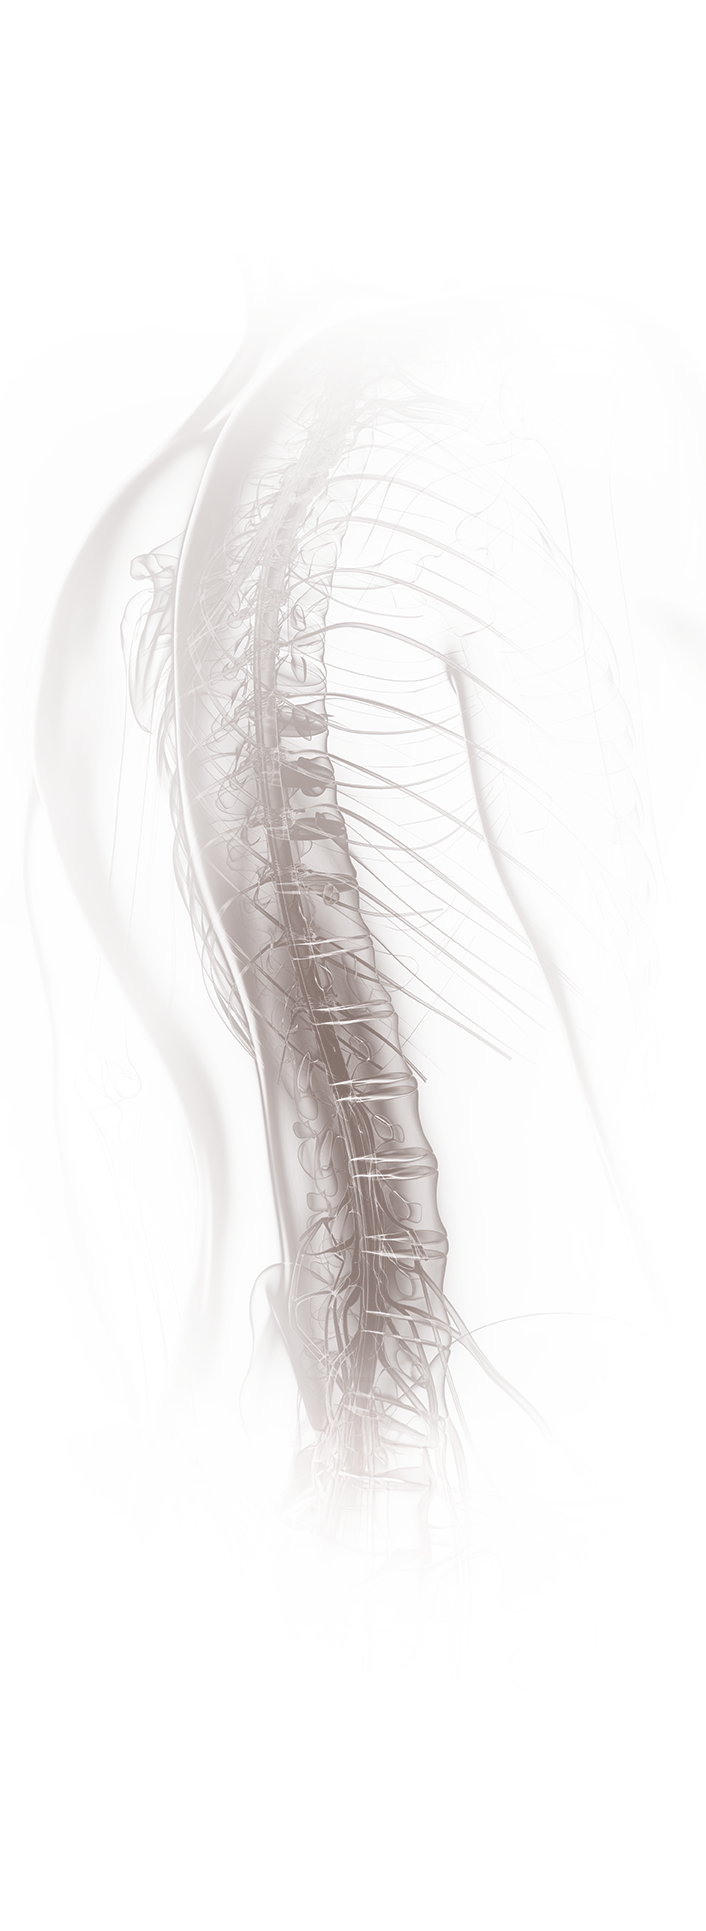

Die endoskopische Wirbelsäulenchirurgie ist eine minimalst-invasive Alternative zur offenen Operation bei verschiedenen Wirbelsäulenerkrankungen. Durch kleine Schnitte und Endoskope ermöglicht sie präzisere und schonende Verfahren. Für ausgewählte Indikationen ist diese Technik bereits heute Standard.